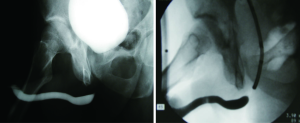

The sensitivity and specificity of RUG for the diagnosis of a urethral stricture has been reported in current literature. Sensitivities between 75% and 100% have been observed, with specificities of 72-97%. Typically, imaging is compared to cystoscopy and intraoperative measurements as a comparison. Positive predictive values have been reported from 50-93%, with negative predictive values varying in the 76-100% range (7-9). As such, retrograde urethrogram is considered to be strong in its ability to diagnose stricture, and further characterize its length, location, and number with a high degree of accuracy. Figure 3 demonstrates proper delineation of a long-segment penile urethral stricture related to lichen sclerosus which was initially assessed as a “meatal stenosis”. A long-segment (5 cm) idiopathic bulbar urethral stricture is demonstrated in Figure 4.